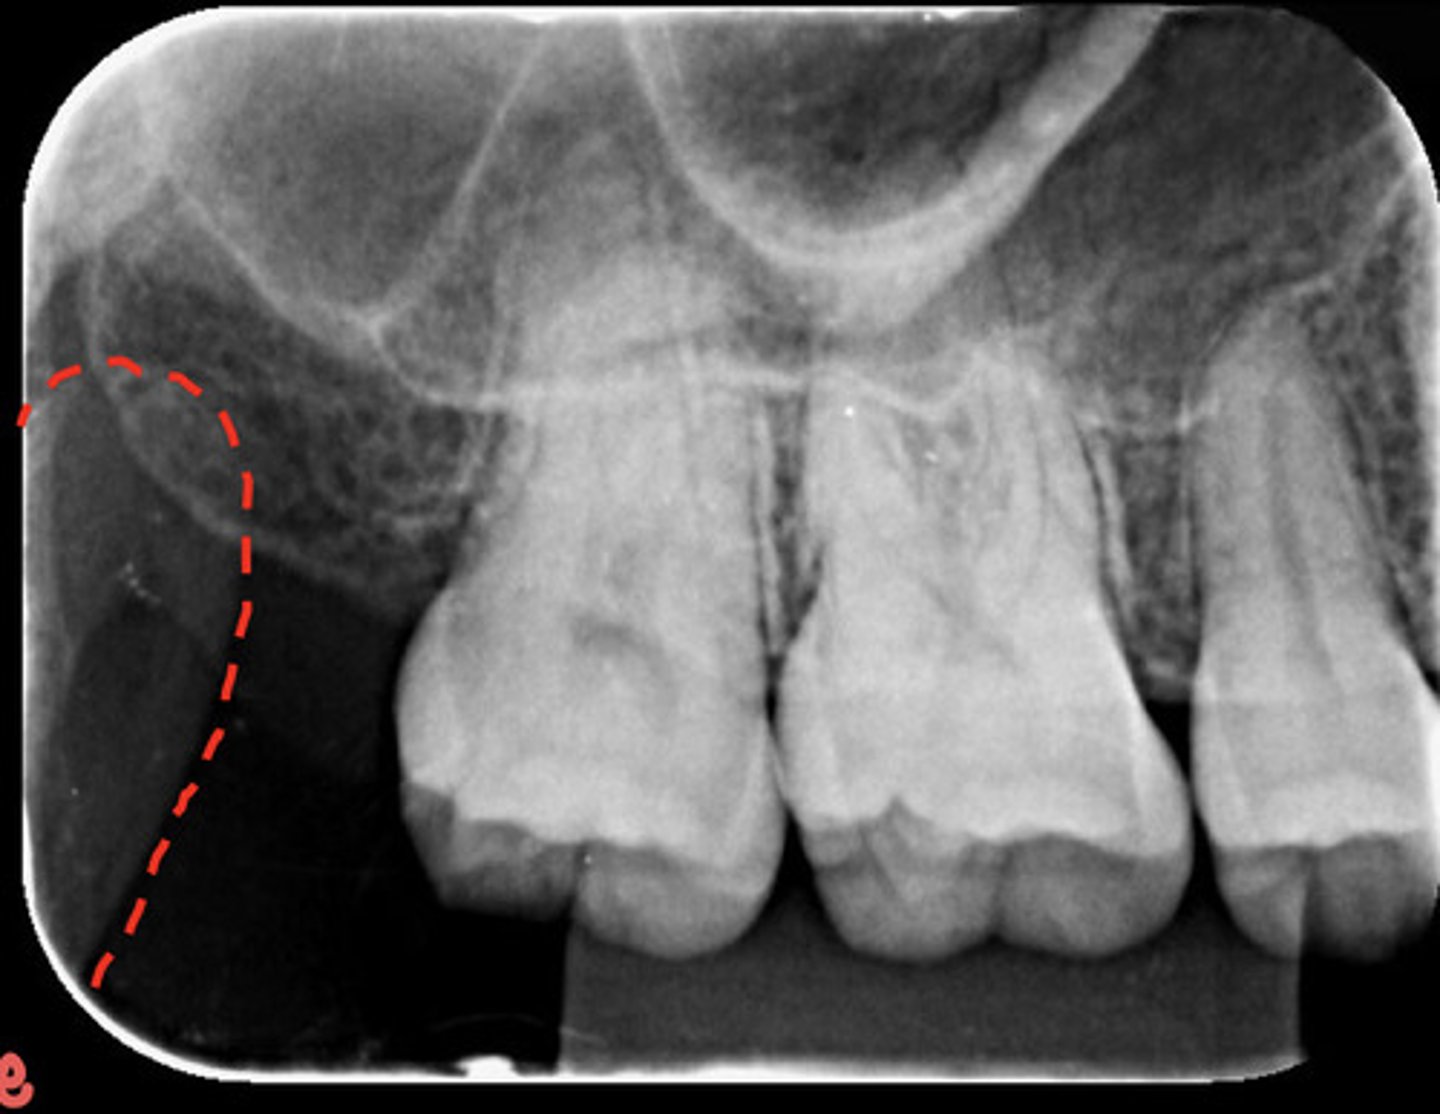

What is the red dotted line circling?

Zygomatic bone

What is the red dotted line representing?

Coronoid process of mandible